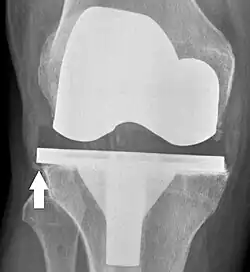

Knee replacement is routinely evaluated by X-ray, including the following measures:

- FFC: frontal femoral component angle. It is typically regarded as optimal when being 2–7° in valgus.[63]

- FTC: frontal tibial component angle, which is regarded as optimal when being at a right angle. A varus position of more than 3° has generally been found to increase the failure rate of the prosthesis.[63] -

- Anterior femoral notching (the femoral component causing reduced thickness of the distal femur anteriorly), seems to cause an increased risk of fractures when exceeding about 3 mm.[64]

- LTC: lateral (or sagittal) tibial component angle, which is ideally positioned so that the tibia is 0–7° flexed compared to at a right angle with the tibial plate.[63]